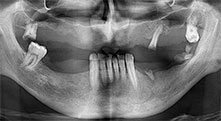

Restbezahnung

Ein 40-jähriger Patient mit desolater Restbezahnung wünscht eine Implantatversorgung. Da er Raucher ist, wird im Oberkiefer kein Sinuslift mit festem Zahnersatz, sondern eine Stegprothese auf vier anterioren Implantaten geplant.

Piezomed B6

Der Kieferkamm wird beidseitig piezochirurgisch gespalten (Instrument: Piezomed B6). Die Implantation erfolgt im selben Eingriff und der periimplantäre Knochen wird zusätzlich mit einer GBR-Maßnahme aufgebaut.

Implantate

Die vier Implantate befinden sich wie geplant in situ. Die distalen Oberkiefermolaren dienen noch zur Fixierung der unterfütterten Prothese, die einen Monat nach Implantation eingegliedert wird.